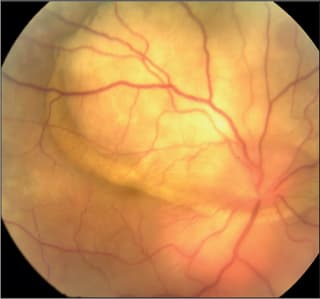

Full-field electro retinography is a crucial test in the monitoring of birdshot retinochorioretinopahy (Figure 1). The bright scotopic response amplitude and 30-Hz photopic flicker-implicit times are sensitive, objective, and reproducible indicators of retinal dysfunction that enable physicians to quantify disease progression and adjust treatment accordingly.5

Figure 1. Birdshot chorioretinopathy with petalloid macular edema imaged by fluorescein angiography.